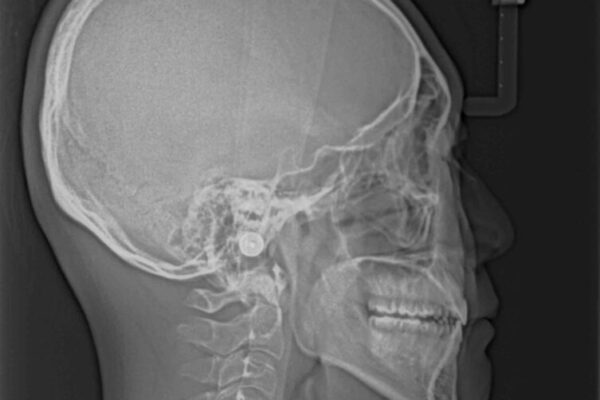

受け口傾向の咬み合わせと口元の突出感を気にして来院された患者様です。

治療計画

受け口傾向特有の狭い上顎歯列であったため、歯列の拡大を補助装置で行い、下顎歯列全体を後方に移動させることとしました。

奥歯の咬み合わせを改善させた後、上下左右の小臼歯(下顎は残存乳歯)を計4本抜歯し、ワイヤー装置にて口元の突出感を改善しながら咬み合わせを整えることとしました。

治療後について

下顎の残存乳歯は小臼歯よりも大きいため、スペースを閉じるために長い期間を必要としますが、予想通りに長期間を要することとなりました。

受け口傾向の方の抜歯矯正は、下顎前歯が舌側に倒れることで歯肉退縮を起こしやすいことが知られていますが、ワイヤーに工夫をすることでリスクを軽減させています。